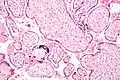

![]() Micrografía de citomegalovirus (CMV) infección de la placenta (placentitis CMV), una infección de transmisión vertical: El característico gran núcleo de una célula infectada con CMV se ve descentrada en la parte inferior derecha de la imagen, tinción H&E. | ||

Además de infectar al feto, los patógenos transplacentarios pueden causar placentitis (inflamación de la placenta) y/o corioamnionitis (inflamación de las membranas fetales).

Placentitis por citomegalovirus (CMV) -

Placentitis por citomegalovirus (CMV)